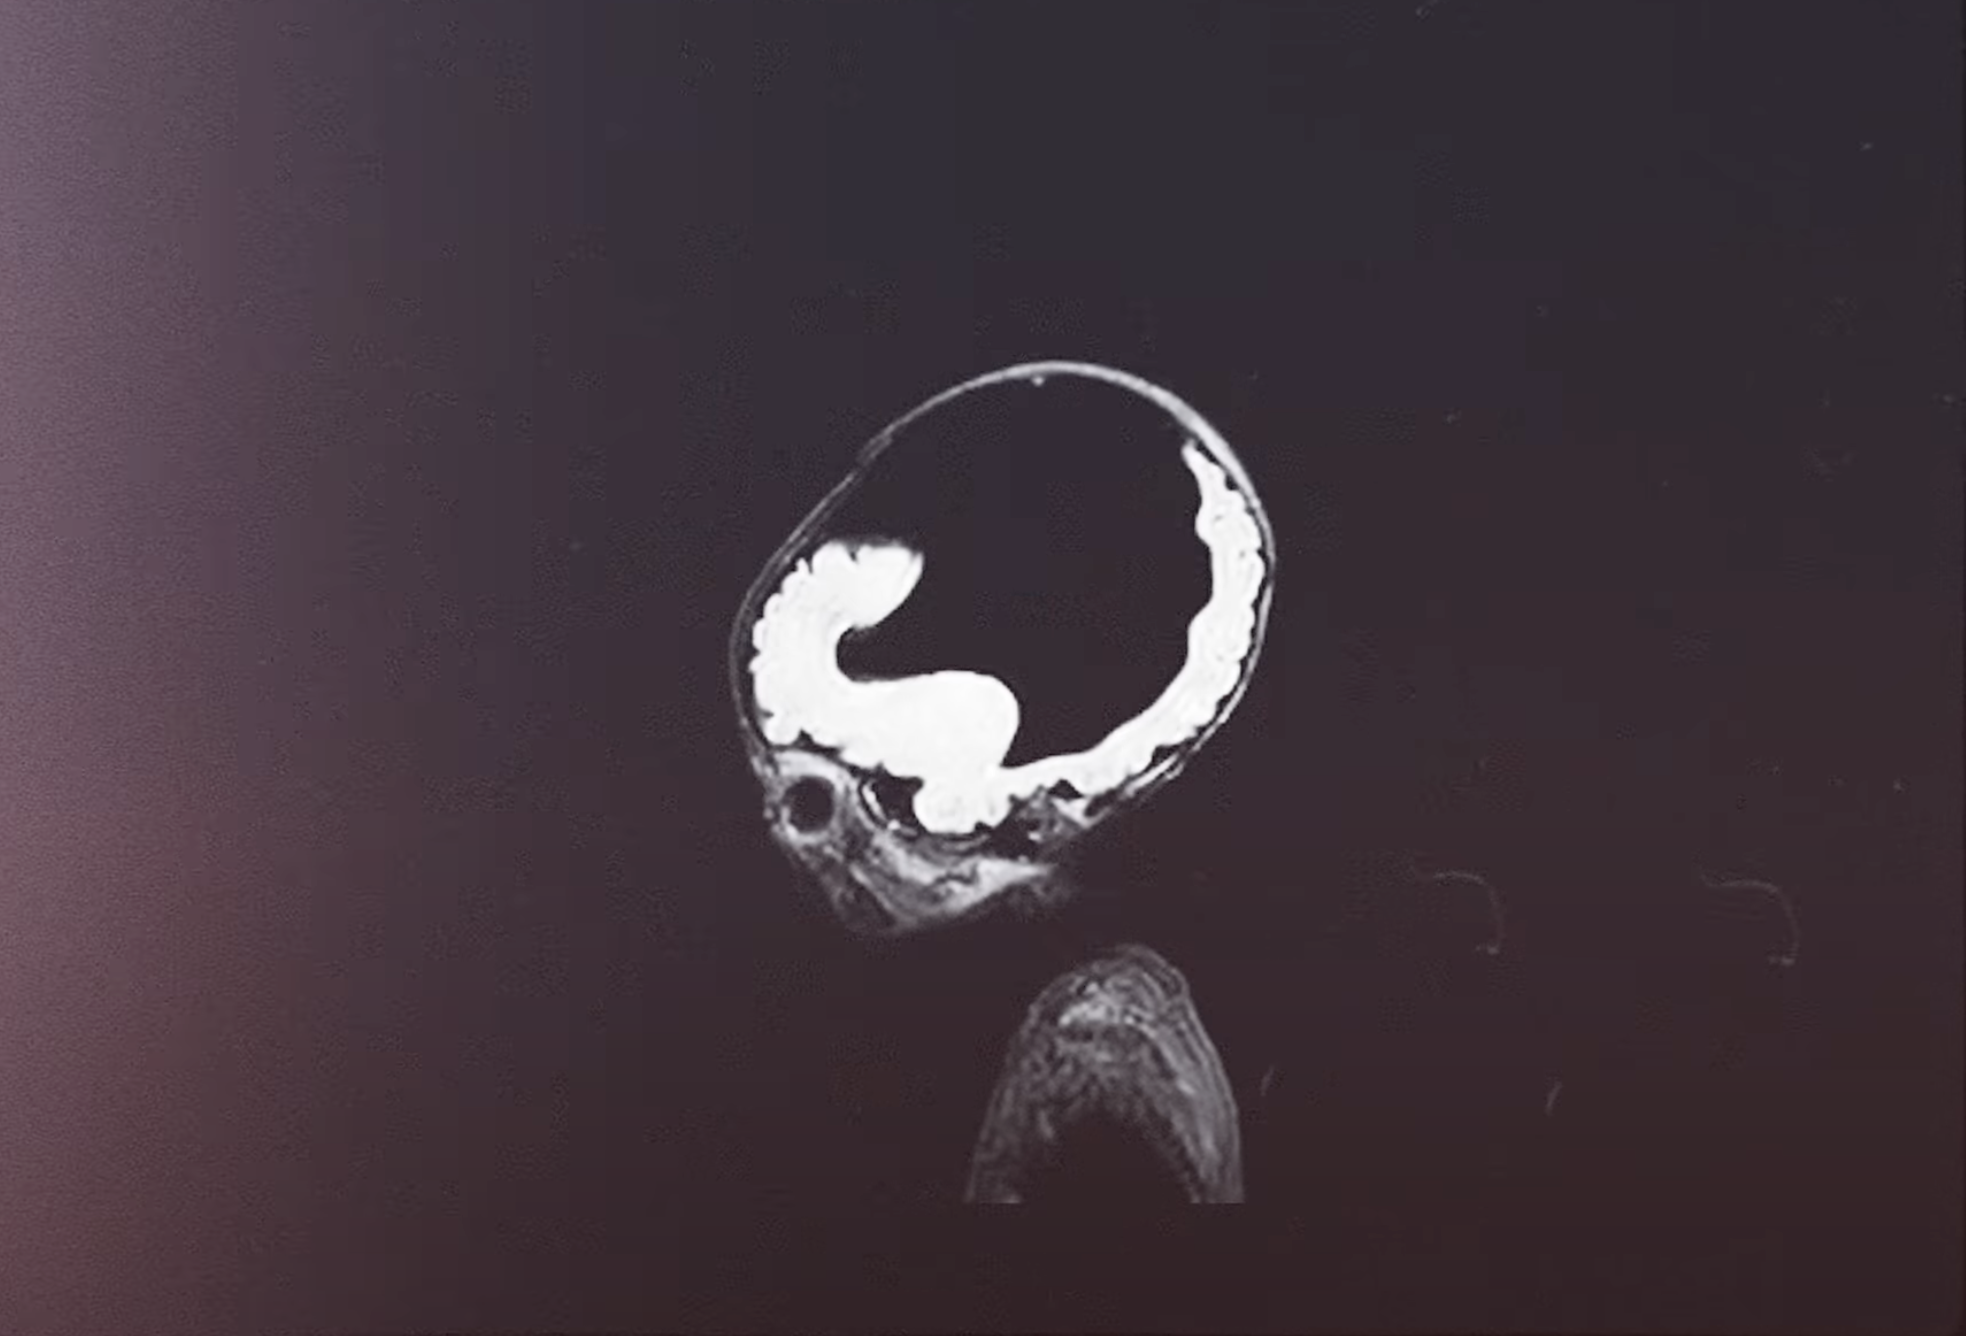

Bei Tomek wurde im Mutterleib Hydrozephalus diagnostiziert. Hydrozephalus, auch als Wasserkopf bekannt, ist eine Erkrankung, bei der sich übermäßig viel Gehirn- und Rückenmarksflüssigkeit im Schädelinneren ansammelt. Dies führt zu einem erhöhten Druck, der auch auf das Gehirn wirkt. Zudem wurde festgestellt, dass ihm große Teile seines Gehirns fehlten. Seine Eltern hätten in ihrem Heimatland Polen eine Abtreibung vornehmen lassen dürfen, lehnten dies jedoch ab, wie LiveAction berichtet.

Obwohl er mit nur einem Zentimeter Gehirn geboren wurde, kann er heute laufen, Worte sprechen und ein relativ normales Leben führen. Tomeks Geschichte wurde im Rahmen der Kampagne „Jedes Leben ist ein Wunder“ von Grupa Proelio vorgestellt, die den Wert jedes menschlichen Lebens hervorhebt.

Seine Eltern bereiteten sich auf das Schlimmste vor und planten, Tomek so lange wie möglich ein schmerzfreies Leben zu ermöglichen, bis er auf natürliche Weise sterben würde. Bei der Geburt war sein Gehirn nur einen Zentimeter groß. Ein Shunt wurde in seinen Kopf eingesetzt, um die Flüssigkeit abzuleiten und ihm Schmerzen zu ersparen – als Teil der Palliativversorgung. Doch dann überraschte Tomek alle: Er lebte weiter. Nach einem Monat waren die Ärzte fassungslos.